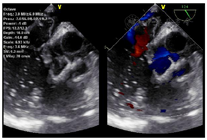

心脏超声:下腔静脉-右房-三尖瓣-肺动脉位人工带瓣管道依序连接,肺动脉人工管道内血流速度约2.3 m/s,压差约21 mmHg,下腔静脉内径约22 mm,略呈椭圆形,随呼吸运动变化幅度减低(图4)。